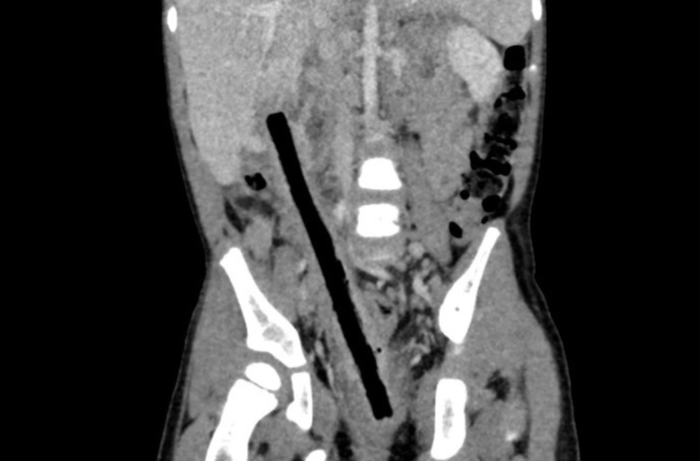

Tại đây, kết quả CT scan cho thấy, bệnh nhân có dị vật kích thước 1x16cm nằm từ trực tràng đến gan. Ê-kíp nội soi xác định, dị vật đâm xuyên trực tràng, ruột non và tá tràng ruột viêm dính nhiều, gây khó khăn cho phẫu thuật.

Các bác sĩ tiến hành mổ mở bóc tách dọc theo dị vật, tách dính toàn bộ ruột, tránh làm tổn thương các mạch máu thần kinh, niệu quản và các bộ phận khác.

Sau 4 giờ phẫu thuật, các bác sĩ đã lấy ra nguyên vẹn cành cây dài 16cm trong ổ bụng bé và xử lý cầm máu, khâu các vết thương, cũng như làm hậu môn tạm. Hiện tại, sức khỏe đang dần hồi phục, dự kiến sẽ sớm được xuất viện, hẹn tái khám và lên kế hoạch đóng hậu môn tạm.